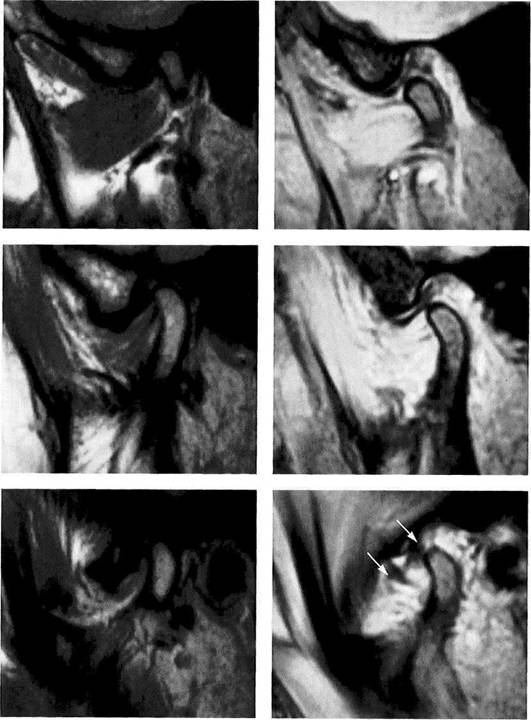

Normal joint

Left: Macroscopic anatomical pre­paration of a right temporo­mandibular joint with normal disk position. The pars posterior (1), pars anterior (2), pars media (arrow), and condyle (3) can be clearly seen.

Right: In spite of the reduction in signal caused by formalin fixation, the corresponding slice in MRI shows the identical relationships between the disk (1,2) and condyle

Medial disk displacement

Left: Formalin-fixed preparation from a right joint. In this anterosu-perior view, the displacement of the disk (arrows) toward the medial is evident.

Lateral pterygoid muscle

Lateral pole

Medial pole

Right: MRI in the angled coronal plane confirms the medial disk po­sition (arrows). The contours of the fossa and condyle are reproduced precisely.

Shape of the pars posterior

Left: Macroscopic anatomical pre­paration of a right articular disk showing its positional relationship to the condyle. The posteroinferior edge of the pars posterior (1) shows a small triangular area of fi­brosis (arrows).

Right: In spite of the sharply re­duced signal emission resulting from formalin fixation, even this type of change is accurately repro­duced (arrows). Here the use of a combination of T1 and T2 weight­ing is often helpful.

Reproduction of Anatomical Detail in MRI

Fibrosis of the bilaminar zone

Left: Formalin-fixed preparation of the centromedial part of a left tem­poromandibular joint with localized fibrosis of the bilaminar zone (ar­rows).

Pars posterior

Right: The MRI accurately repro­duces the abnormality (arrows) dis­tal to the flattened pars posterior. The contour of the condyle is indi­cated by a broken line.

Presumed "posterior disk displacement"

Left: Macroscopic preparation of a left temporomandibular joint with normal positioning of the pars an­terior (1) and pars posterior (2) in the lateral portion of the joint. The retrodiskal structures appear thick­ened.

Right: In an MRI there appears at first glance to be a posterior disk displacement (arrows). Under clos­er inspection, however, it can be seen that the pars anterior (1) and pars posterior (2) lie in correct rela­tion to the condyle.

Left: A view of the disk and the bil­aminar zone after further prepara­tion again reveals the correct posi­tional relationships. Here the pars anterior (1) and pars posterior (2) can be identified more readily. The presumed "posterior disk displace­ment" is a false positive interpreta­tion of the fibrosis of the bilaminar zone (arrows).

Right: MRI of the same joint shown in Figure 427.

Disk perforation and osteoarthrosis

Left: Anatomical preparation of a left temporomandibular joint with arthrotic changes (black arrows) and extensive disk perforation (white arrows). In the anterior re­gion only a part of the former pars anterior (1) can still be recognized.

Right: MRI shows similar conditions. The cortical layer of the arthrotic condyle is thickened extensively (arrows). The remainder of the pars anterior (1) can still be distin­guished.